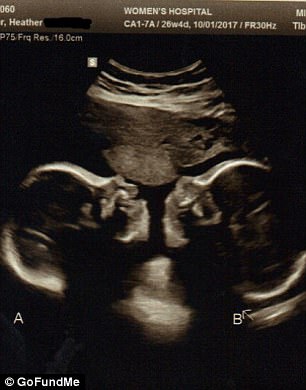

CINCINNATI – A Cincinnati, la famiglia Kroeger ha dato il benvenuto a Elijah ed Isaac, una coppia di gemelli siamesi uniti in modo tale che qualsiasi intervento per separarli sarebbe rischioso. A Heather e Jason, i genitori, che hanno altri cinque figli, era stato detto che la donna avrebbe potuto abortire ma non l’hanno pensato nemmeno per un momento: “Per noi non era un’opzione e non lo sarà mai”, ha detto il papà a Fox19.